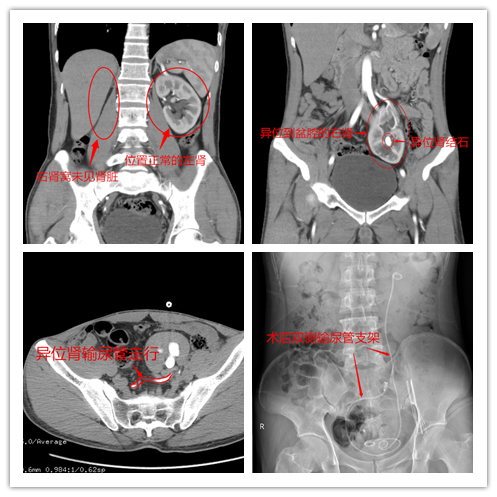

通过入院后的泌尿系CT增强检查显示,患者异位右肾位于盆腔左侧,在左盆腹交界区,异位右肾结石并右肾积水。且右侧肾脏异位到左侧盆腔压迫到了左侧输尿管。

由于患者异位肾的输尿管是横向,拐了好几个弯,输尿管镜硬镜进不去;结石较大大,输尿管软镜手术时间会太长;又因右侧异位肾与腹壁之间肠管较多,经皮肾穿刺损伤肠管风险会增大。综合患者情况,医疗团队制定了个性化治疗方案,对患者行腹腔镜引导下行盆腔异位肾经皮肾镜钬激光碎石取石术+左输尿管镜检的双镜联合手术。

术中,杨科主任与袁武雄主任发现患者左侧输尿管中段有狭窄,成功置入输尿管支架进行支撑扩张,并对异位肾的结石进行了清除。手术不到2个小时,顺利完成。术后,患者恢复良好,痊愈出院。